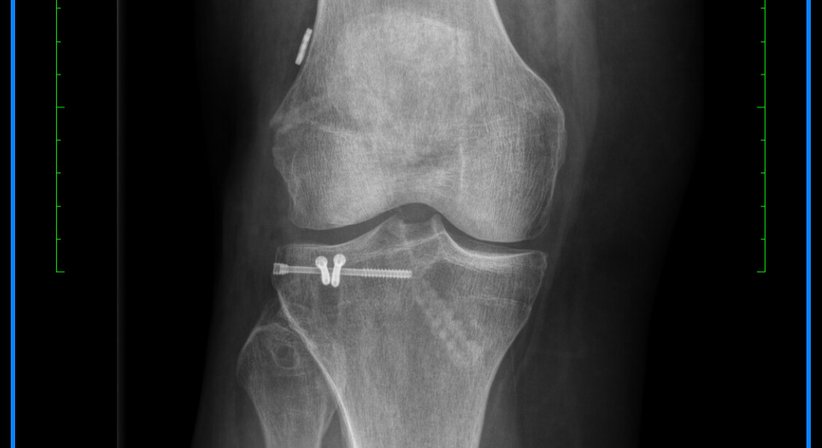

Behandlung von Frakturen des Ober- und Unterschenkels im Kniegelenksbereich